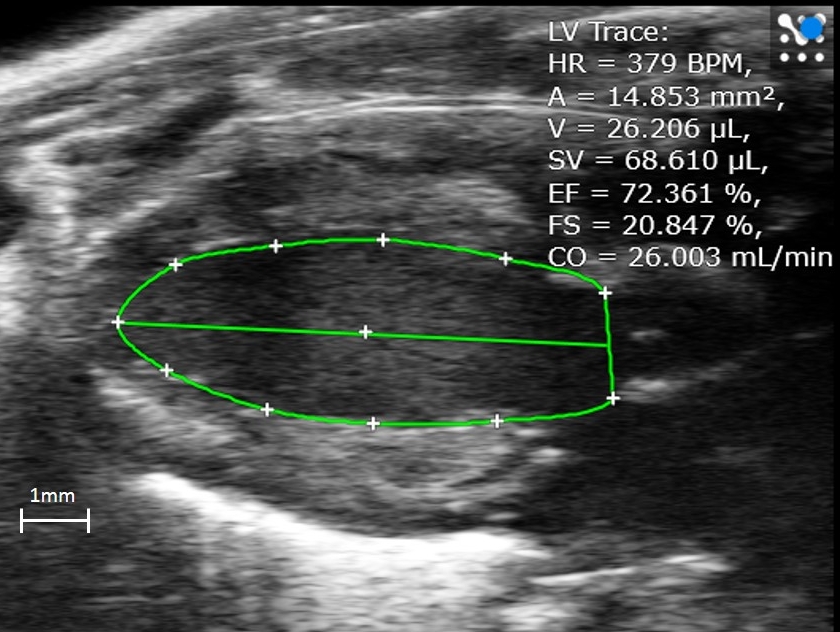

文献和实验1、【仪器名称】:小动物超声成像系统。 2、【仪器型号】:Vevo 770。 3、【生产厂家】:visualsonics Co. Ltd. 4、【检测适用范围】:该系统为一套小动物灰阶及血流参数的影像系统,用来进行小动物胚胎及肿瘤血流的评估。利用高频超音波精细的分辨率对人体及小动物各表层组织的观察已经开始被广泛的应用